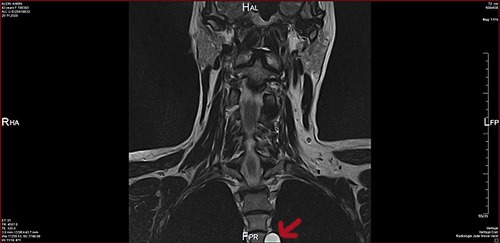

… hab ich heute keinen in meiner Neuro-Praxis, wahrscheinlich sind sie nicht da gewesen. Aber ich hab meine CDs durchgesucht, da war leider keine neuere BWS dabei. Also hab ich mir die HWS-Aufnahmen vorgenommen und siehe da: auf den Bildern von 11/2020 sieht man das Ding auch schon deutlich. Auf den Bildern von 2019 ist der Wirbel nur noch ansatzweise drauf, da kann man was erahnen, aber nicht sicher sehen. Und auf meinen BWS-Aufnahmen von 2016 war noch nichts zu erkennen.  Mal sehen, ob ich Montag jemanden in meiner Neuro-Praxis oder der Radiologie dran bekomme um zu erfahren, ob das Teil schon in dem Bericht von November erwähnt wird.

Nicht gerade klein, das gute Stück …